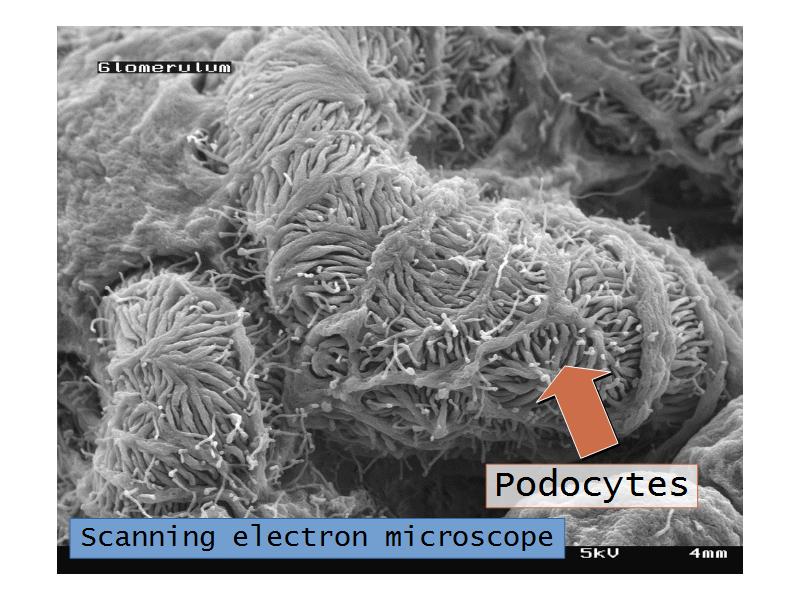

- The renal corpuscle

Nephron